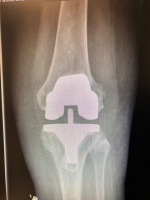

He performs a large number of partial knee replacements, many of which can be carried out as day case procedures. These minimally invasive operations typically allow faster recovery and now offer durability comparable to total knee replacement in suitable patients.